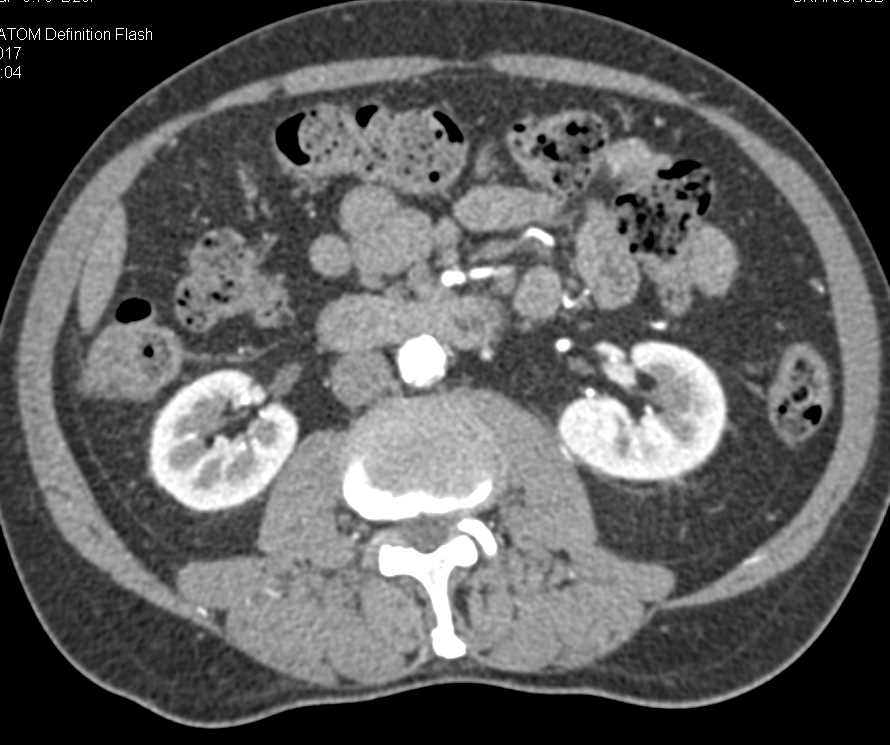

Bowel Changes S/P Left Nephrectomy